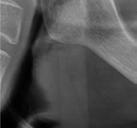

En la ortopantomografía se aprecia una dentición permanente a falta de la erupción de los 2os y 3 os molares, así como una asimetría ósea con rama y cóndilo mandibular izquierdo menos desarrollado (figura 9), causante de la asimetría facial descrita anteriormente.

Figuras 9-11.